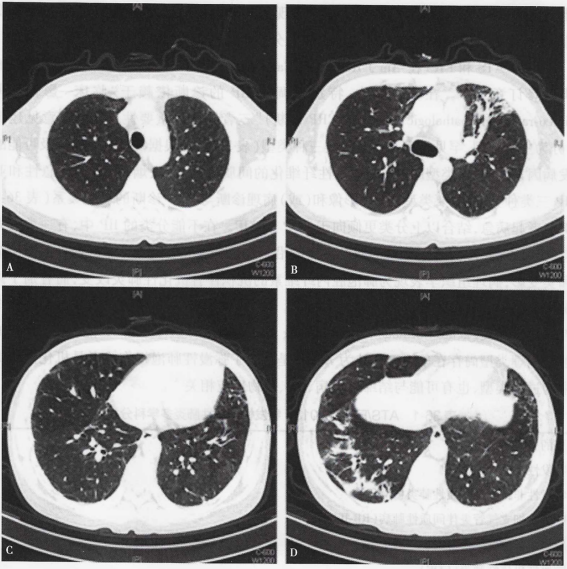

经上述治疗3 d后患者体温峰值波动在38℃以下,神志转清,复查动脉血气分析,氧合较前明显改善,自主呼吸试验通过气道保护能力尚可。2017年1月6日拔除气管插管并复查胸部CT及头颅CT。胸部CT提示两肺病变较2016年12月28日进展,左肺体积较前变小,纵隔左偏,右下肺实变较前加重(图2),头颅CT未见明显异常。

图2  胸部CT提示两肺病变较前进展